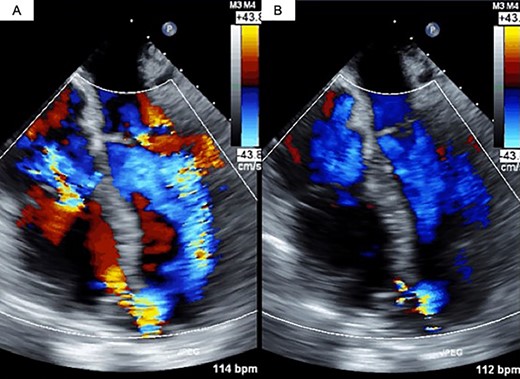

The decision was made to proceed first with PAB to stabilize the hemodynamics and delay the timing of surgical repair. After median sternotomy, PAB was attempted with a 4-mm wide Teflon felt band. The size of the band was adjusted to where the left to right shunt disappeared under transesophageal echocardiographic guidance (Fig. 1). Postoperative echocardiography revealed a bidirectional shunt through the VSR (Qp/Qs = 1.3), and the chest radiography showed decreased pulmonary congestion (Fig. 2). Cardiac output was maintained to allow adequate end-organ perfusion after PAB (urinary output >100 ml/h). Surgical VSR closure with the infarct exclusion technique and coronary artery bypass grafting were performed 7 days after PAB. The PAB was released after the initiation of cardiopulmonary bypass. Through the infarction area of the left ventricle, the right and left sides of the VSR and infarcted area were approached and covered with a bovine pericardial patch. No residual left to right shunt was observed on transesophageal echocardiography. On postoperative Day 32, the patient was discharged to a rehabilitation hospital.

Transesophageal echocardiography findings. (A) Pre-PAB; (B) post-PAB